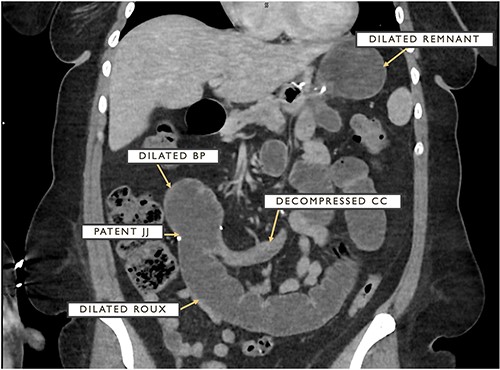

The patient underwent an urgent diagnostic laparoscopy with a noted herniation of the CC in between a 2-cm defect from the Brolin stitch and the stapled closed common enterotomy of the jejunojejunostomy. The anatomic landmarks and site of herniation are depicted in a different patient in Fig. 2. This herniated bowel was carefully and successfully reduced laparoscopically with subsequent visible decompression of previously dilated roux and BP limbs and remnant stomach. The defect was carefully closed with two simple-interrupted stitches with care taken not to narrow the JJ anastomosis or CC outflow. Further suction decompression of the bowel was completed by intentional enterotomies involving the BP and roux limbs that were then inconsequentially stapled, excised and removed. Her hospital course was complicated by an ileus requiring the placement of a decompressive remnant gastrostomy tube by interventional radiology on post-operative day 2. Following the resolution of her ileus, this remnant gastrostomy tube was clamped around the clock and her diet was slowly advanced. The patient was discharged uneventfully on post-operative day 5 with good pain control and diet tolerance.

The arrow depicts the location of defect enabling herniation of CC between JJ anastomosis and Brolin’s stitch with relative locations for BP and roux limbs.